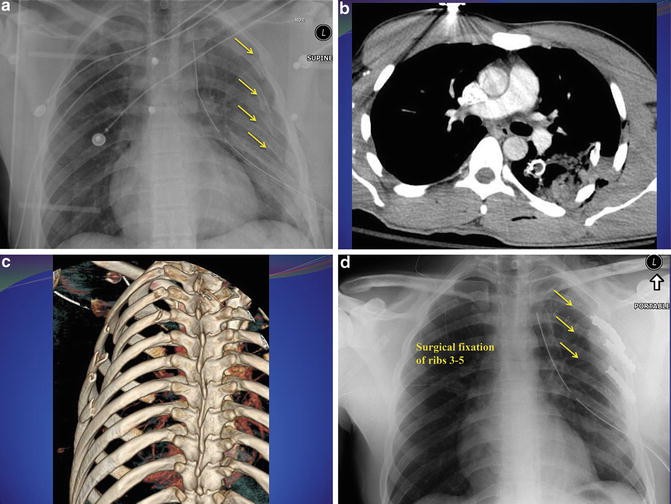

Introduction, Epidemiology, and Definition of Chest Wall Injuries Meaning Of Chest-Unexpanded fef50% and unexpanded (ue) as well as expanded (e) chest measurements in males was inferred from the observations. find out the ideal measurement of your chest for your height and consult a personal trainer if you wish. as in our study, mean chest expansion values decreased gradually but significantly with age, apart from a slight. a. Meaning Of Chest-Unexpanded.